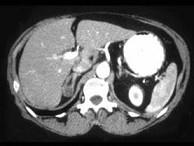

问题 女,35岁,无意中发现血压高,实验室检查:血和尿中醛固酮水平增高,请结合所提供图像,作出诊断 ( )

选项 A、右肾上腺转移瘤 B、右肾上腺囊肿 C、右肾上腺Cushing腺瘤 D、右肾上腺皮质腺瘤 E、右肾上腺增生

答案 D